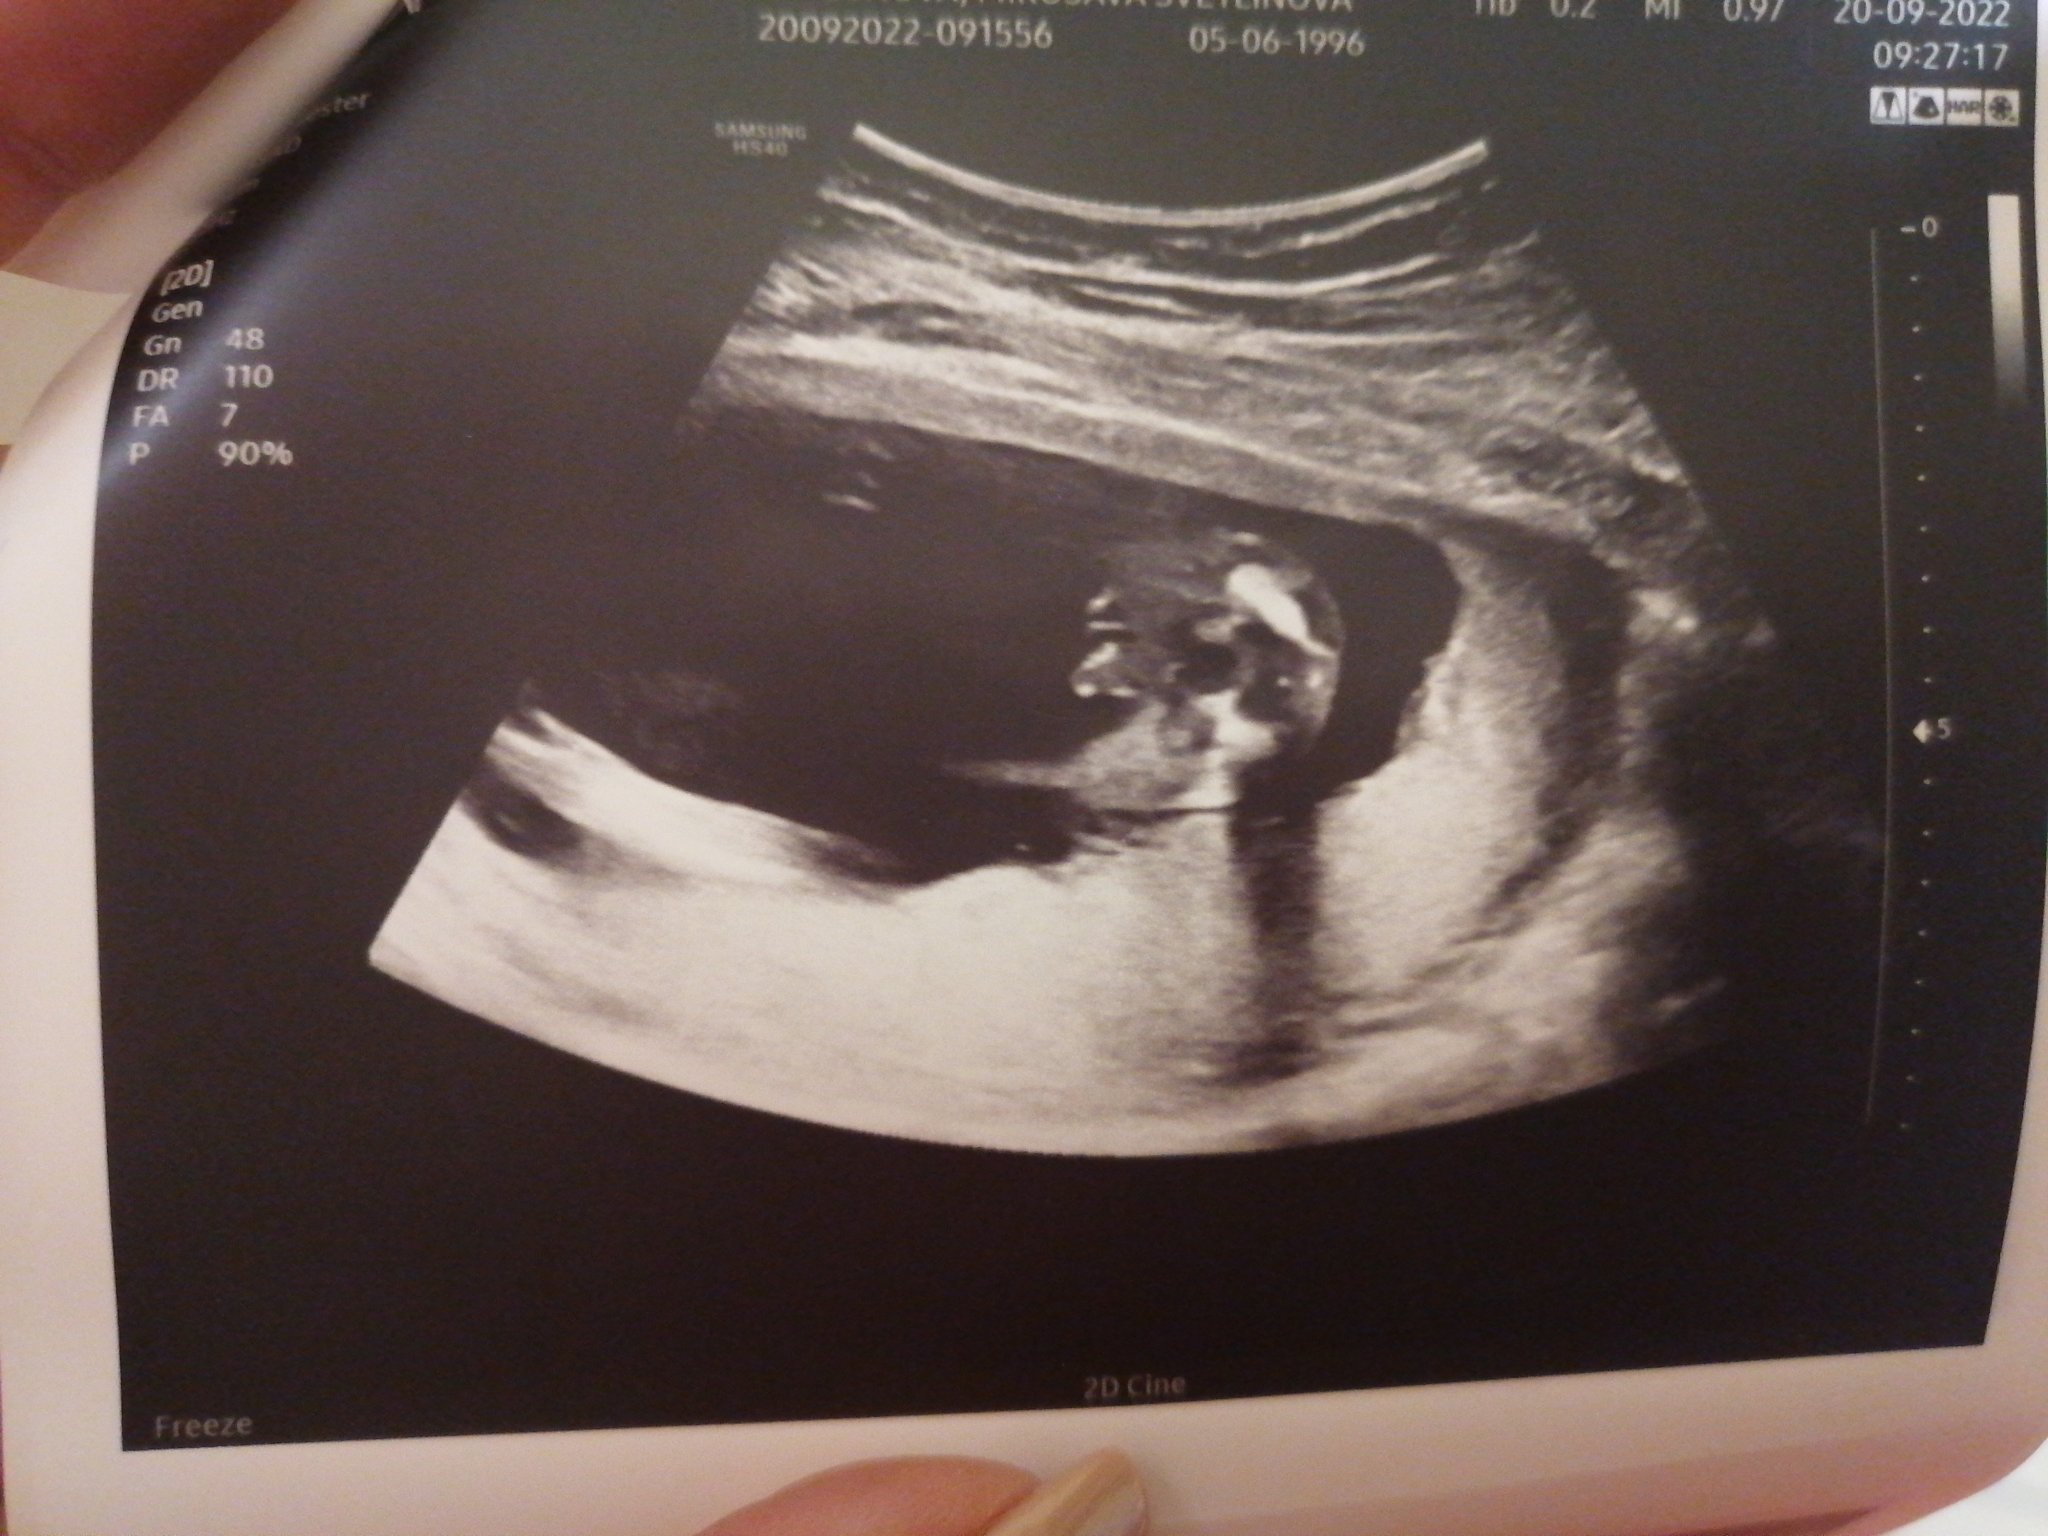

Какво представлява феталната морфология и защо е важна?